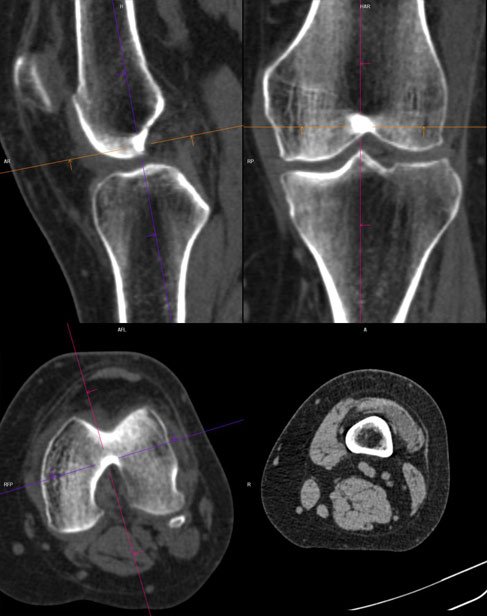

De obicei, pentru articulatii/ oase, se folosesc imagini cu doua tipuri de parametri diferiti: pentru parti moi si pentru os.

Imaginile cu parametri de părți moi (“kernel” dedicat părților moi) sunt de obicei cu contururi mai line, mai “smooth”, cu “netezirea” artificială a micilor detalii și permit reconstrucții 3D foarte plăcute ochiului, cu aspect anatomic.